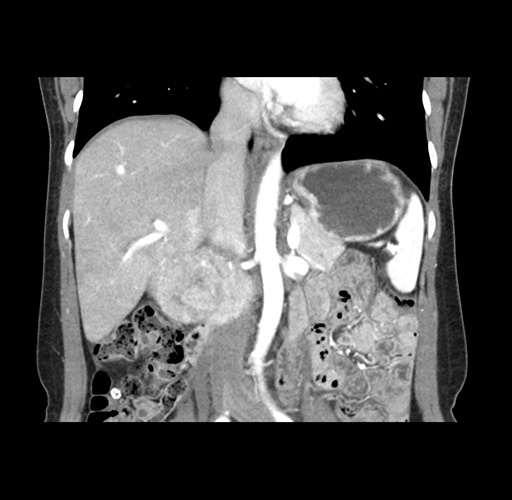

Imaging Analysis

Look through the patient's CT scan to identify any areas of concern for the necessary procedure.

Based on your CT findings, which issue(s) would give reason for "planned slowing down moment(s)" in this case?

Considering a standard left lateral sectionectomy procedure, what step(s) of the operation would you do differently in this case ?